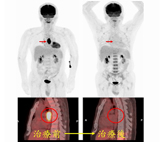

此男性病患在發現食道癌後接受了去氧葡萄糖正子掃描以作為分期及治療前評估。治療前發現食道有ㄧ段明顯葡萄糖代謝升高的腫瘤病灶。經過醫師給予合併化療與放射治療之後,可以看見原本呈高葡萄糖代謝性的食道腫瘤幾乎已經消失,明顯反應出有效治療的成果。病患後續接受追蹤及治療中。